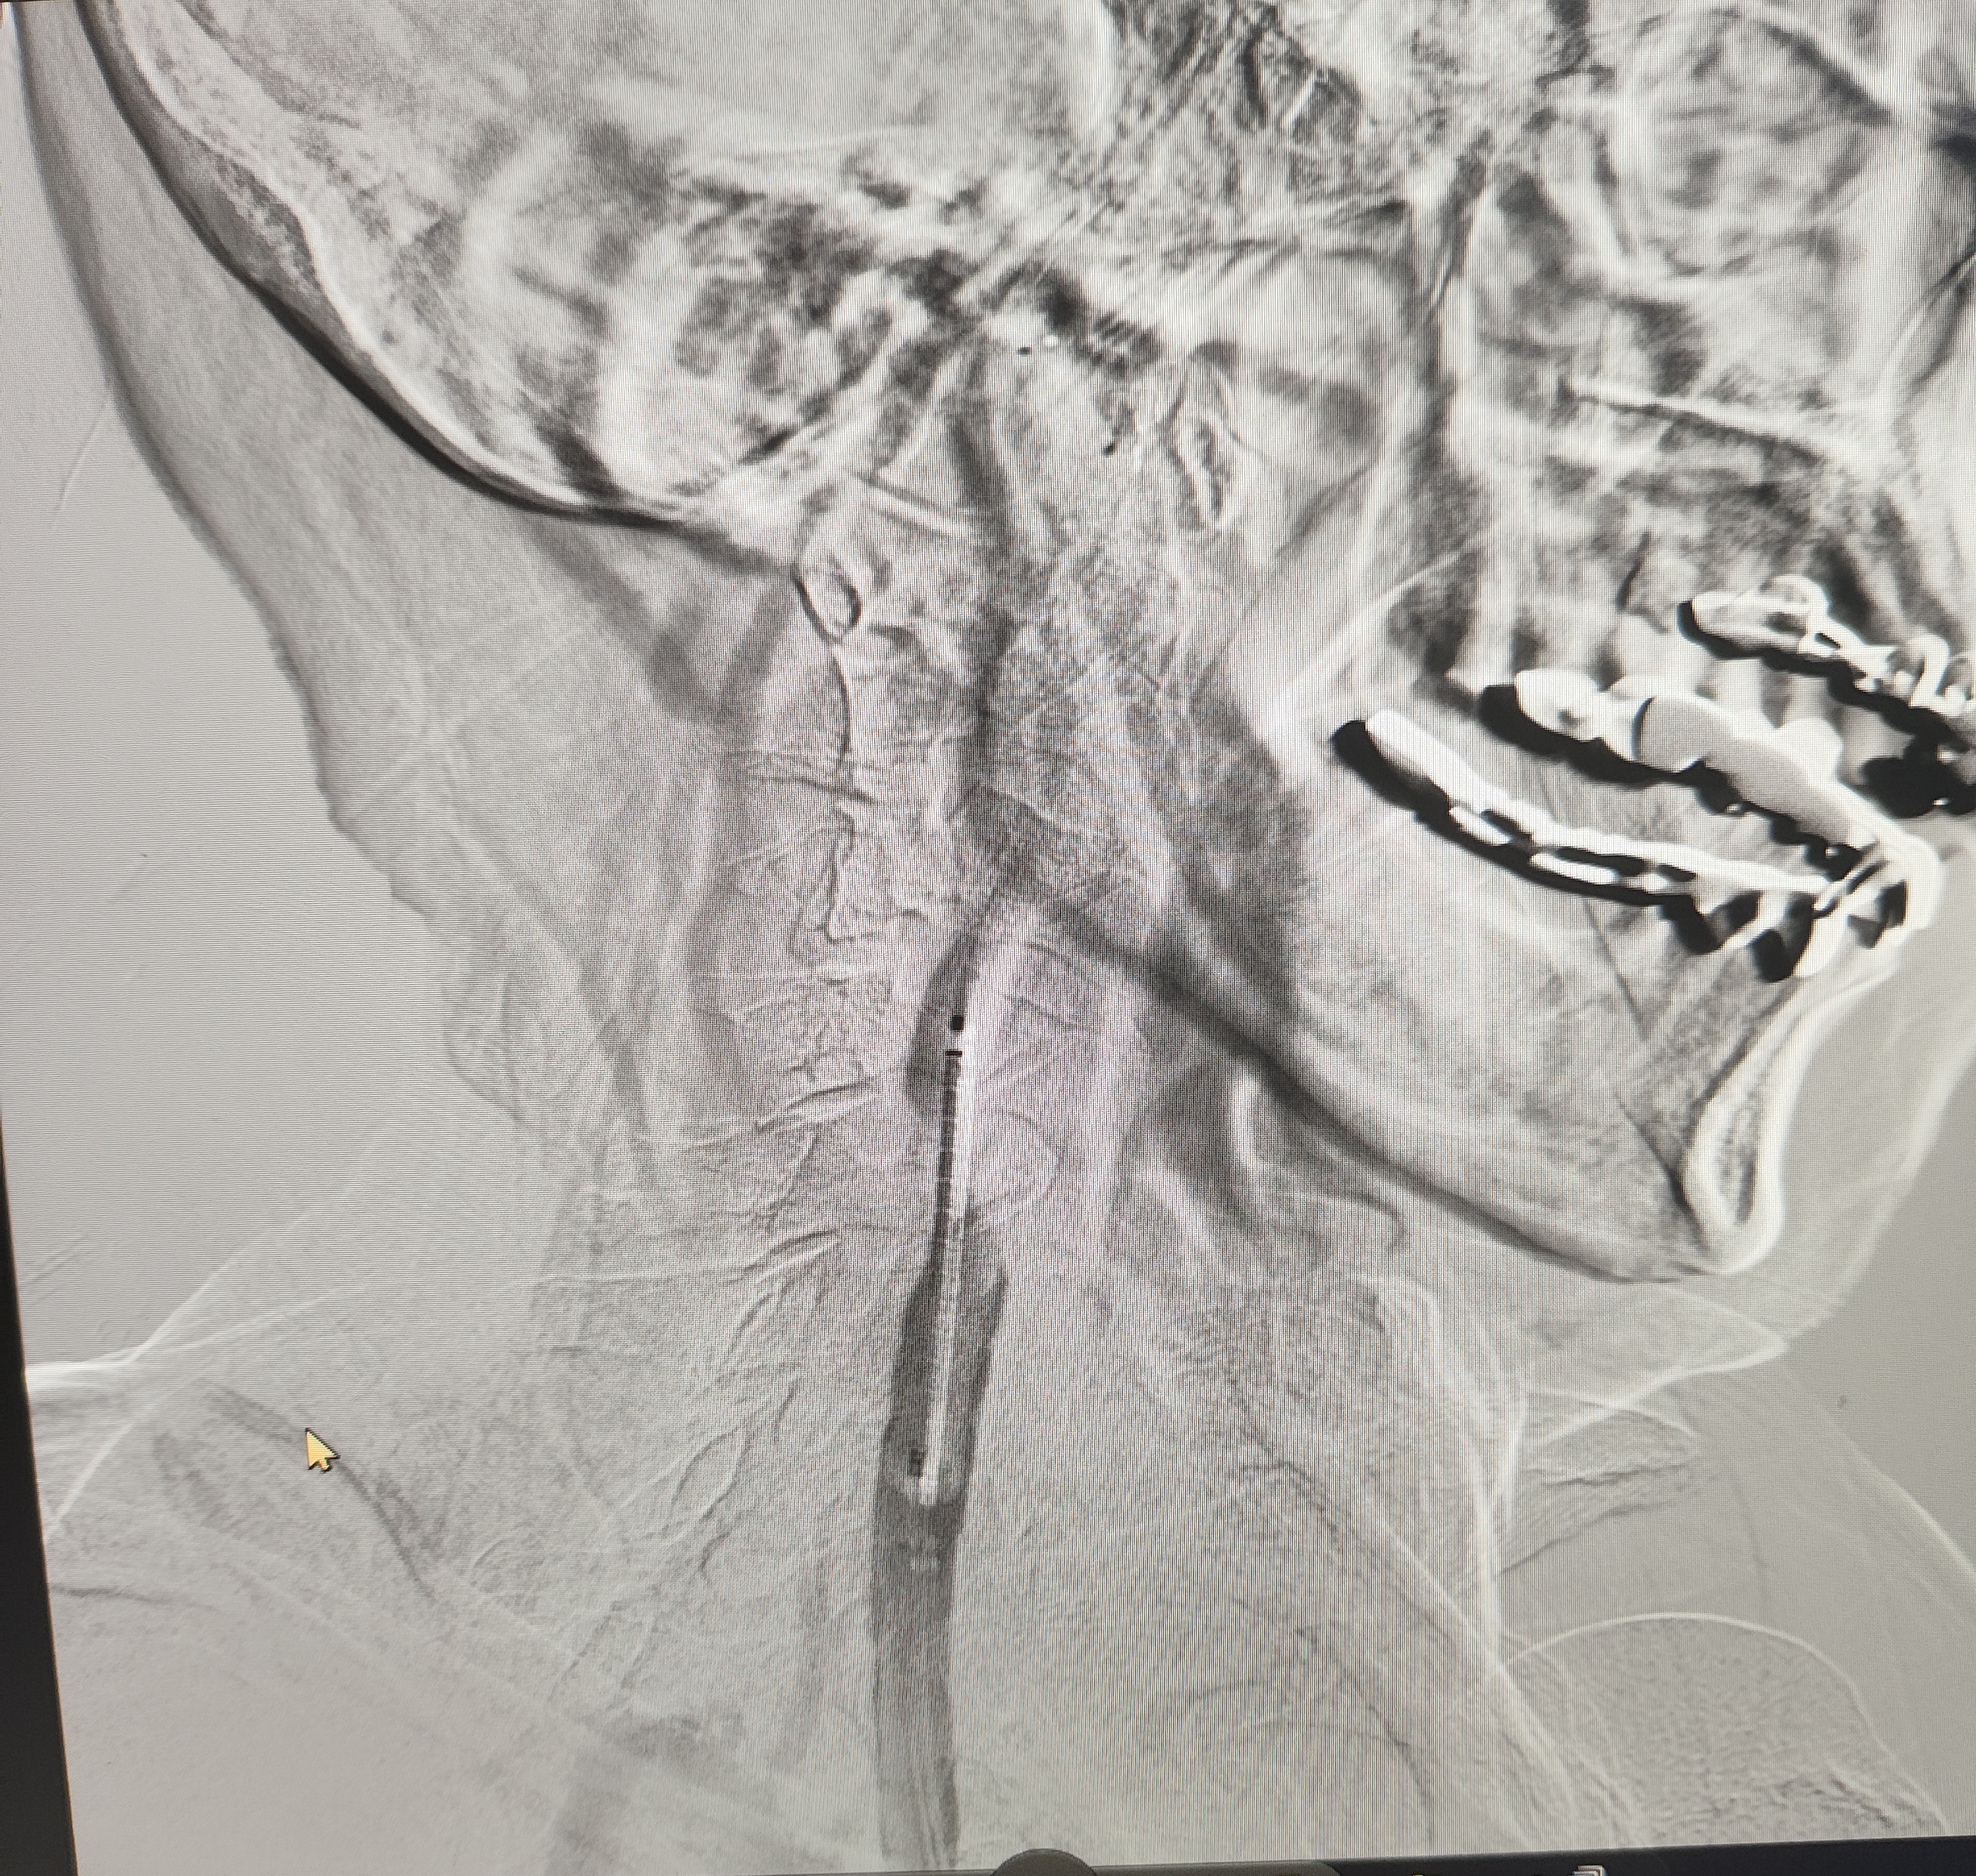

颈总巨大斑块急性闭塞的血管内治疗(双颈动脉支架桥接+支架释放后掉斑块,抽吸取栓)

84岁男性,既往右侧颈动脉狭窄病史8个月,多次脑梗未治疗,本次突发左侧肢体无力来诊,发病30小时后转入我院。

症状进行性加重,意识逐渐模糊,烦躁,左上肢肌力1级,左下肢肌力2级,当地考虑开通难度大,转入我院。

急诊上台。